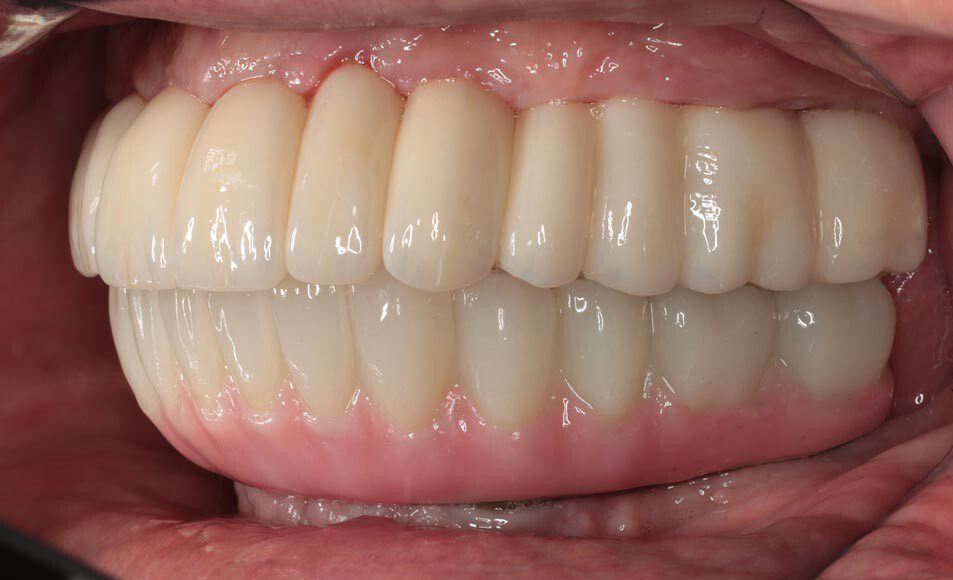

Frontal temporary smile. The patient heals for two additional months and returns to start the process for fabrication of the permanent implant bridges. We begin by assessing and photographing the temporary bridges. There are several issues with the first temporary bridges. Mainly, because he wore his original denture after the first surgery, we were unable to correct the left-to-right cant (slant) until now.